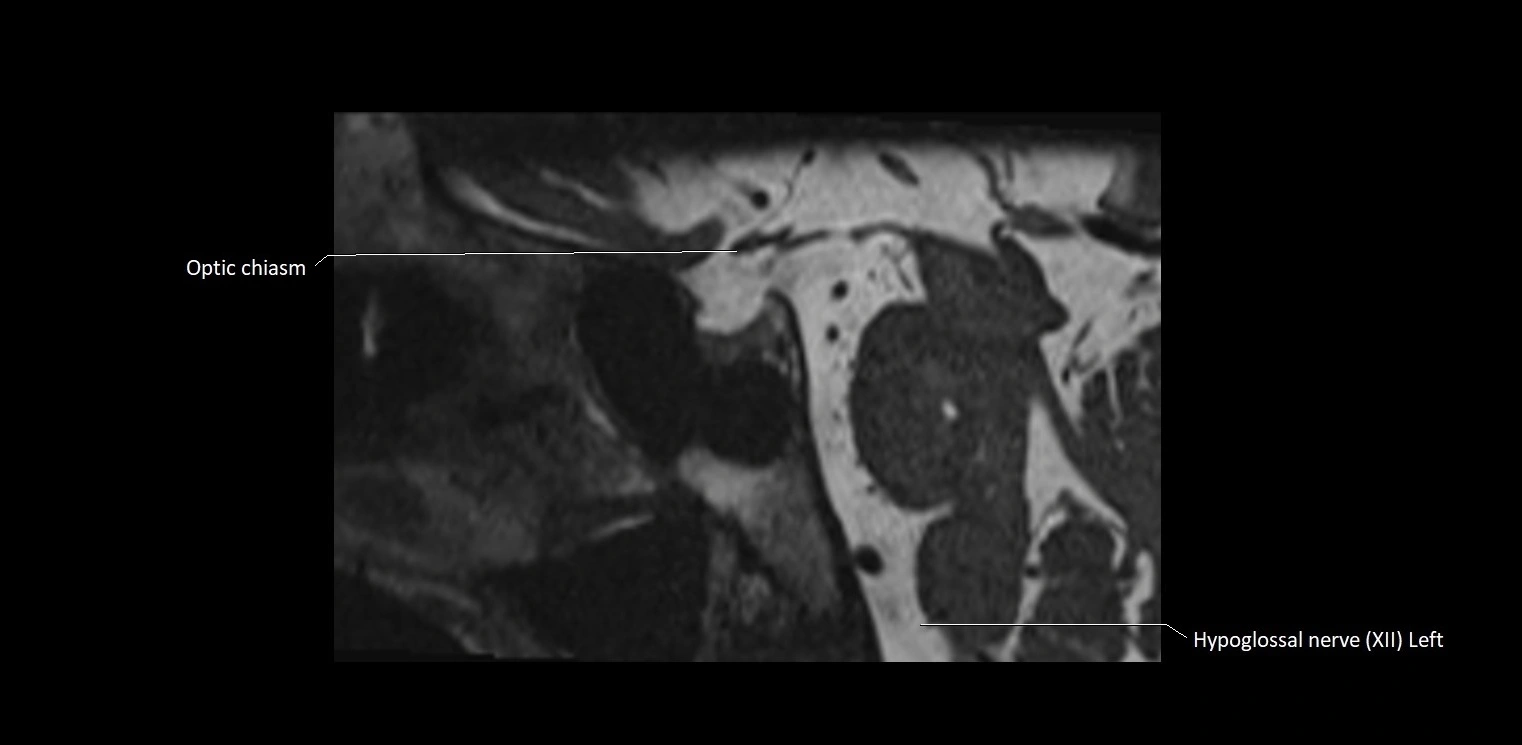

MRI Appearance

• The abducens nerve is a small, thin, linear structure

• Best visualized on high-resolution T2-weighted 3D MRI sequences (e.g., FIESTA or CISS)

• Seen as a hypointense (dark) line running from the brainstem at the pontomedullary junction, traversing the prepontine cistern, and entering Dorello’s canal under the petrosphenoidal ligament, then into the cavernous sinus, and finally the orbit

• May be challenging to visualize in standard MRI due to its small size

• Pathology may be inferred by absence, displacement, or enhancement of the nerve